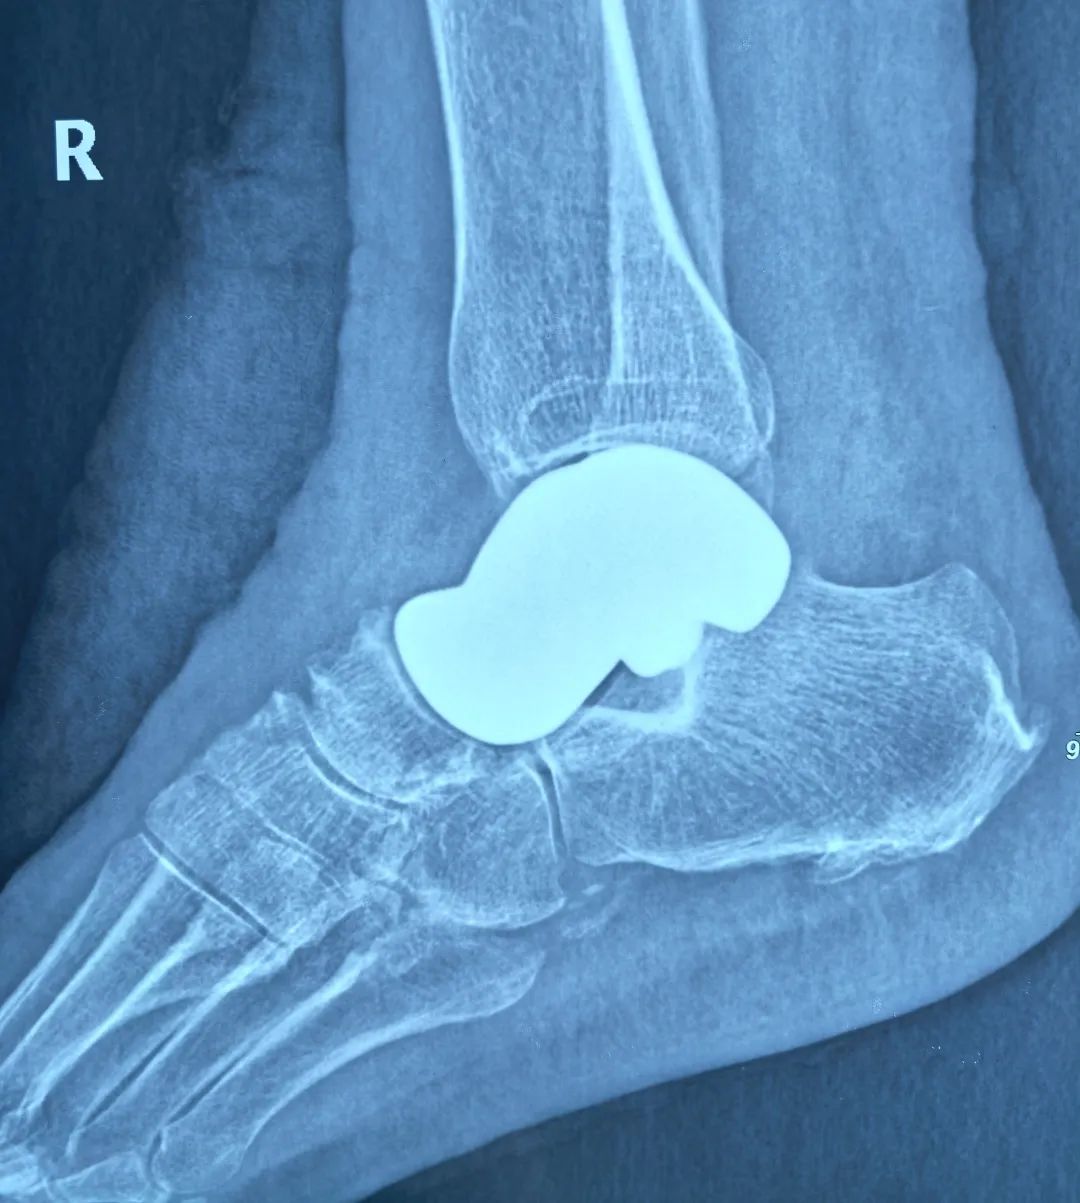

今年年初,来自普洱市景东县的郑阿姨在江川探望女儿期间,因足踝剧痛无法行走,在女儿与女婿的陪伴下,来到江川区医共体总医院骨科就诊。经检查,确诊为右足距骨坏死,需行“3D打印全距骨置换术”。

“我们通过3D建模技术,对患者的距骨进行1:1数字化复刻,结合生物力学分析精准计算骨骼的生理曲度、受力点等参数,最终定制出与患者结构完美契合的专属假体。”江川区医共体总医院骨科主任杨勇介绍说,作为人体足部的“承重枢纽”,距骨承担着缓冲震荡、维持平衡的关键功能,一旦发生严重坏死或损伤,传统治疗手段往往面临假体适配难、术后恢复差等困境。尤其是传统的距骨假体往往是标准化生产,难以满足每个患者的个性化需求。而3D 打印的假体能够精准匹配患者的骨骼结构,大大减少了手术过程中对周围组织的损伤,同时也提高了假体的稳定性和使用寿命。

今年1月,在云南省第一人民医院专家团队的全程指导与紧密协作下,江川区医共体总医院骨科团队凭借精湛技艺,将经过精密打印、毫米级误差校准的全距骨假体,稳稳植入到郑阿姨体内。